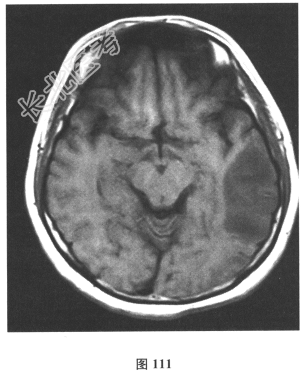

脑脊液检查:常规、生化均正常,CSF-病毒TORCH(-),抗Hu、Yo、Ri均阴性,OB、MBP正常。血清抗Hu、Yo、Ri均阴性。颅脑MRI显示左颞枕、右顶枕多发长T₁、长T₂信号,Flair高信号,病变累及皮质及皮质下白质,病灶无强化,见图108~图114。)根据颅脑MRI,需要鉴别的疾病应是